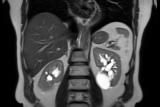

Почечно-клеточная карцинома, наиболее распространенная форма рака почки, как правило, на момент обнаружения уже неоперабельна. Стандартная медикаментозная терапия обычно позволяет выиграть менее года жизни...